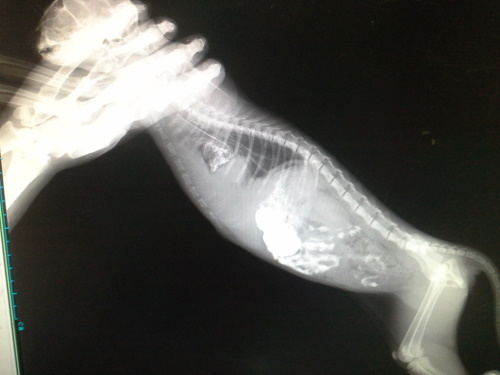

主題: 貓咪求助醫療協助 申請者姓名: 郭崑杉 花色: 申請日期: 2014-08-05 14:36:35 申請者部落格: 申請者臉書網址: 所在縣市/合作醫院: 新竹市/新竺動物醫院 治療費用: 17950元 需求人數: 20人 已結案 (2014-11-12 11:48:35) 報名人員: Patrick x2(已付款)、Wendy Kao(已付款)、JuJu x4、JuJu x2、JuJu x3、JuJu x3(已付款)、Ivy Hsu(已付款)、lavinia x2(已付款)、Ed Tsai x2(已付款)、peiyu(已付款)、Bella Hung(已付款)、chiawei(已付款)、薛、薛(已付款)、Bow Huang x2(已付款)、Fionna Hsu x2(已付款)、胡衿綾(已付款)、 候補人員: 動物病情說明: 這隻白灰貓咪呼吸非常急促,本來以為是鼻氣管炎,7/17送醫治療,貓咪偏瘦,喘,鼠蹊處瘀血,貓瘟檢驗陰性,Xrays顯示胸腔有異物,懷疑橫膈赫尼亞肝臟進入胸腔中,且血檢肝指數偏高,小貓精神食慾非常好,擔心但時間拖久了對貓咪不利,於7/28手術,術中發現肝臟在胸腔中,已有黏連狀況發生,雖然手術順利完成,但因為胸腔的壓力改變,身體無法負荷於術後死亡。